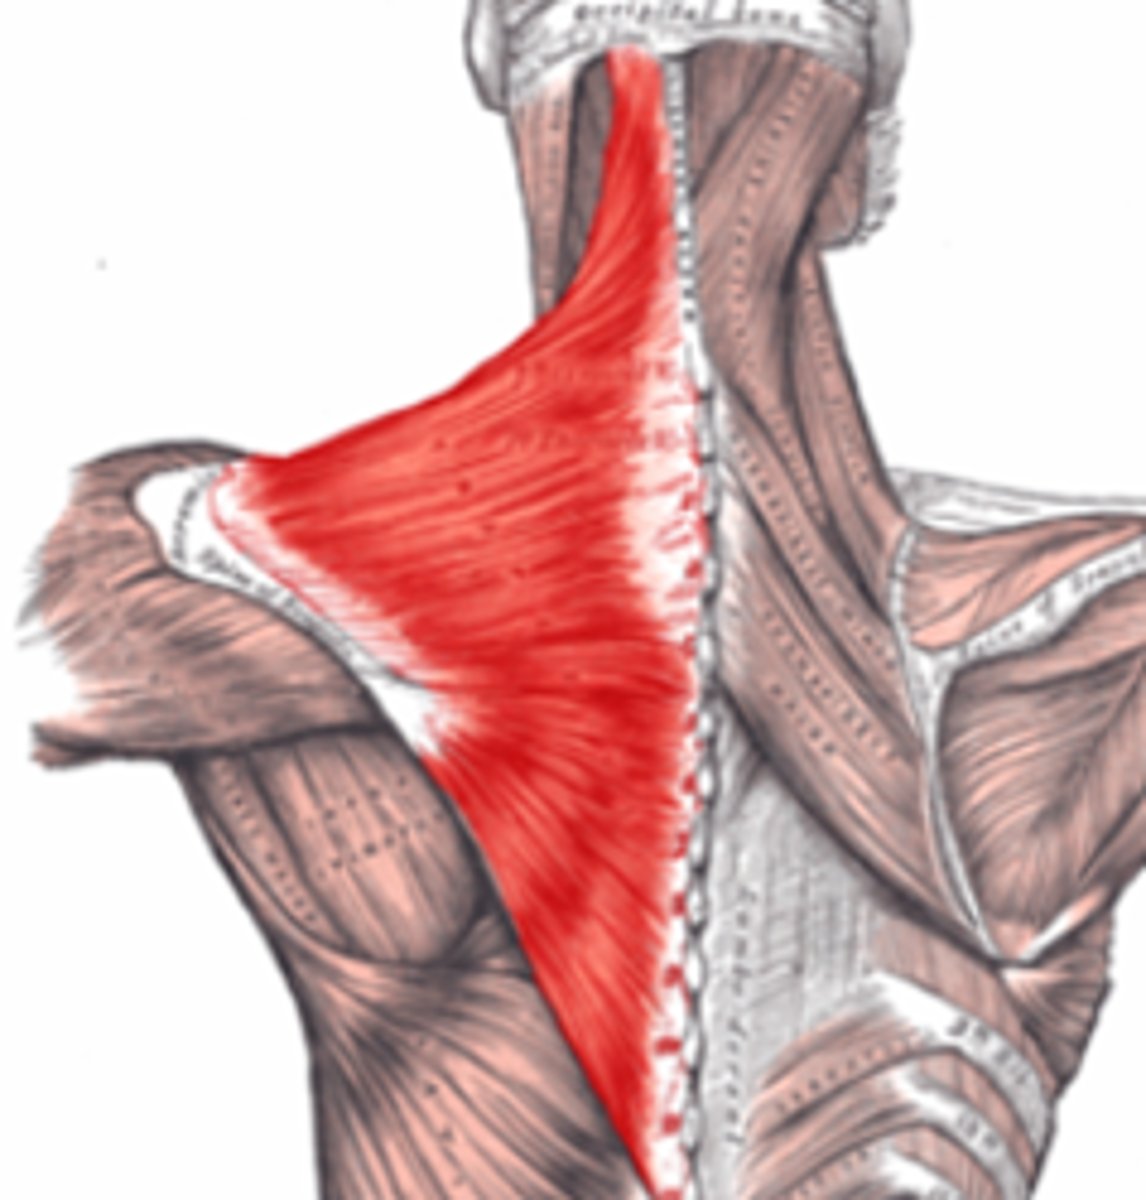

trapezius

elevates, depresses, retracts, and rotates the scapula; rotates the arm